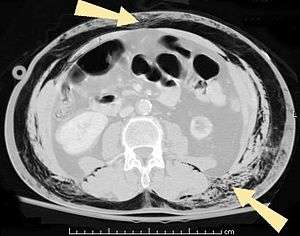

| An abdominal CT scan of a patient with subcutaneous emphysema (arrows) | |

Significant cases of subcutaneous emphysema are easy to diagnose because of the characteristic signs of the condition.[1] In some cases, the signs are subtle, making diagnosis more difficult.[13] Medical imaging is used to diagnose the condition or confirm a diagnosis made using clinical signs. On a chest radiograph, subcutaneous emphysema may be seen as radiolucent striations in the pattern expected from the pectoralis major muscle group. Air in the subcutaneous tissues may interfere with radiography of the chest, potentially obscuring serious conditions such as pneumothorax.[19] It can also and reduce the effectiveness of chest ultrasound.[28] On the other hand, since subcutaneous emphysema may become apparent in chest X-rays before a pneumothorax does, its presence may be used to infer that of the latter injury.[13] Subcutaneous emphysema can also be seen in CT scans, with the air pockets appearing as dark areas. CT scanning is so sensitive that it commonly makes it possible to find the exact spot from which air is entering the soft tissues.[13] In 1994, M.T. Macklin and C.C. Macklin published further insights into the pathophysiology of spontaneous Macklin's Syndrome occurring from a severe asthmatic attack.